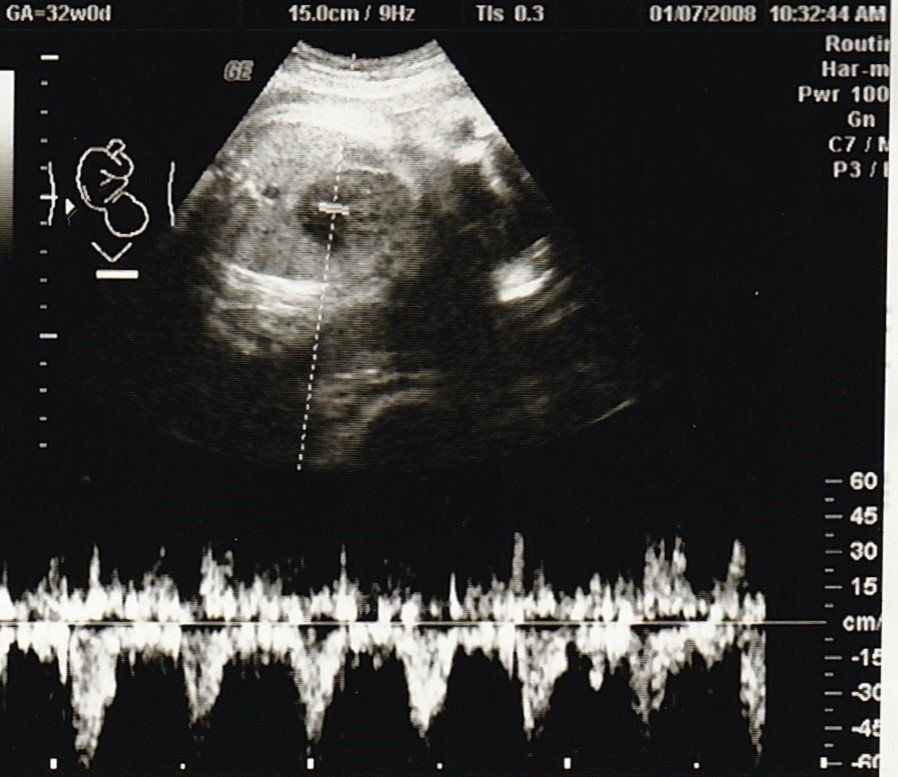

妊娠32週目のエコー写真

2000gを超えました。安心と同時に、体の重い状態がまだあと2カ月も続き、まだ大きくなるのかと思うと少し憂鬱に。体重も7kg以上増え助産師さんに注意されたものの、何か口に入れていないと気持ち悪くなるような状態で、つい食べ過ぎて自己嫌悪になることもありました。